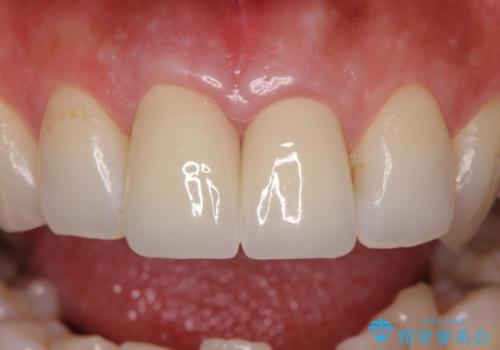

先端に透明感のあるかぶせ物を装着することで審美的な問題を解決しつつ、少しガタついていた歯並びも改善することができました。

- 右上1/再根管治療66,000円+ファイバーコア22,000円+仮歯11,000円+ジルコニアクラウン(スタンダード):121,000円 左上1/仮歯11,000円+ジルコニアクラウン(スタンダード)121,000円 合計352,000円(税込)費用は治療当時の料金となります